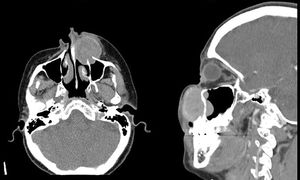

Mujer de 37 años con tiempo de enfermedad de 9 meses, caracterizado por la presencia de una tumoración en la región nasogeniana izquierda de crecimiento rápido. La tomografía con contraste de macizo facial muestra una lesión sólida, homogénea, de márgenes parcialmente definidos, dependiente del maxilar superior izquierdo (figs. 1 y 2).

La biopsia reportó tumor de células gigantes (TCG). Los TCG óseos son lesiones caracterizadas por la presencia de células gigantes multinucleadas y representan el 4% de todos los tumores óseos. Solo el 2% se origina en el esqueleto craneofacial, los de origen maxilar son excepcionales. El tratamiento estándar es la resección quirúrgica.